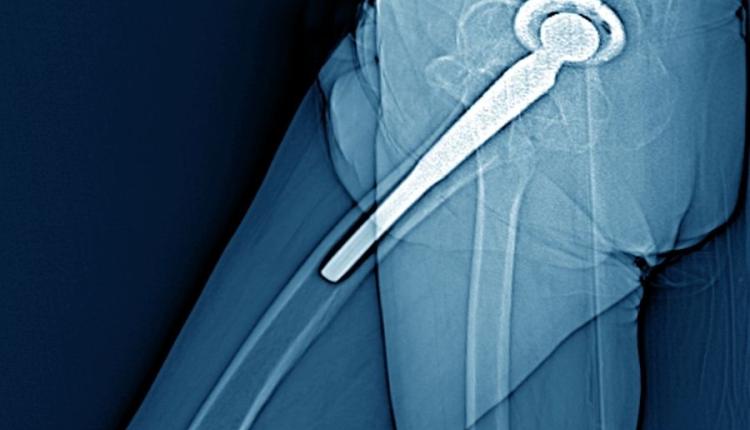

Robotik Kalça Protezi

Kalça eklemi, vücudun ağırlığını taşıyan ve hareket kabiliyetini sağlayan en önemli yapılardan biridir. Yaşlanma, aşırı yüklenme, doğuştan gelen şekil bozuklukları ya da travmalar sonucunda kalça ekleminde ciddi deformasyonlar meydana gelebilir. Bu durumda kalça protezi kaçınılmaz hale gelir. Geleneksel cerrahi yöntemler uzun yıllardır başarıyla uygulanmakla birlikte, son dönemde gelişen teknoloji sayesinde Robotik Kalça Protezi daha hassas ve güvenli bir alternatif sunmaktadır.

Robotik kalça protezinde, tıpkı diz protezinde olduğu gibi hastanın kalça anatomisi önceden detaylı olarak analiz edilir. Bu analiz sonucu elde edilen 3 boyutlu haritalar, cerrahın protezi en doğru pozisyonda yerleştirmesine olanak tanır. Bu durum, hem protezin ömrünü uzatır hem de hastanın doğal yürüyüş ve hareket kabiliyetine en yakın şekilde iyileşmesini sağlar.

Robotik destekli ameliyatların en büyük avantajlarından biri, ameliyat sırasında minimum doku hasarı ile işlemin tamamlanabilmesidir. Kalça bölgesi vücudun hareketli ve büyük kas gruplarını barındırdığı için, geleneksel cerrahilerde bu kaslara zarar verme riski daha yüksektir. Ancak robotik sistemle yapılan ameliyatlarda, kas ve bağ yapılarının korunması ön planda tutulur. Bu sayede hasta daha az ağrı hisseder ve iyileşme süreci hızlanır.

Ayrıca Robotik Kalça Protezi uygulamaları, ileri yaş grubunun yanı sıra genç ve aktif bireyler için de büyük avantaj sağlar. Spor yaralanmaları sonrası ya da doğuştan gelen kalça deformitelerinde tercih edilen bu yöntem, kişiye özel çözümler sunar. Bu sayede hasta, hayatına daha erken dönme şansı bulur ve uzun süreli kullanım konforu yaşar.